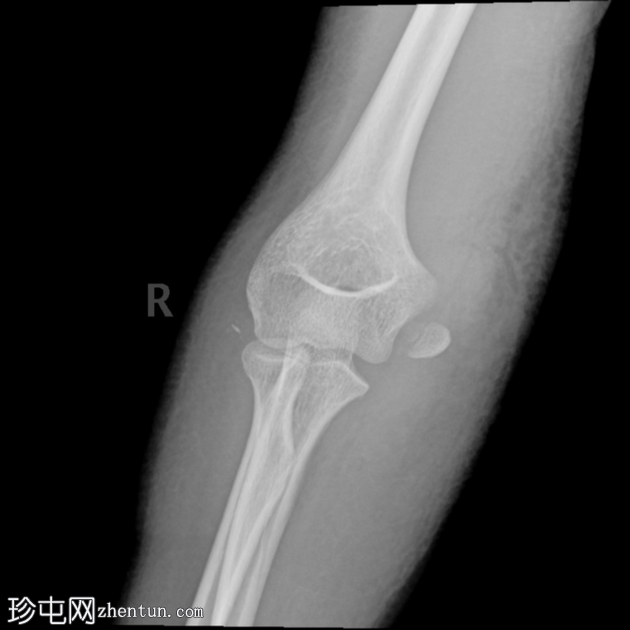

正位片

关节对位不良。桡骨和尺骨外侧脱位。

肘关节内可见骨碎片(正位/侧位片)。

肘关节积液(帆状征)。

桡骨头附近可见碎裂性骨折。